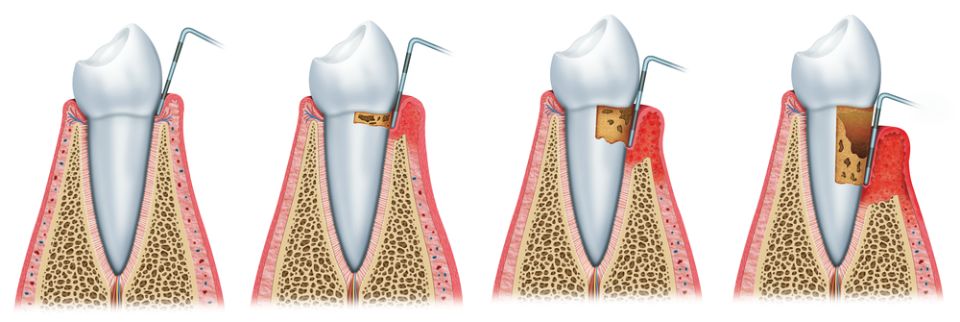

La Periodoncia es la especialidad odontológica dedicada al estudio del periodonto o la estructura de soporte de los dientes. Engloba la prevención, el diagnóstico y el tratamiento de las enfermedades que afectan a estos tejidos que rodean y sujetan el diente al hueso (encía, cemento radicular, ligamento periodontal y hueso alveolar).

Dentro de las enfermedades periodontales más conocidas encontramos:

La gingivitis que cursa con inflamación y enrojecimiento de las encías y posible sangrado al cepillado.

La periodontitis clínicamente presenta los signos de la gingivitis pero también se acompaña de la pérdida de los tejidos que soportan el diente: el ligamento periodontal y el hueso alveolar, causando la movilidad del diente y futura pérdida de éste si no se trata.

Las causas de la periodontitis son la combinación de la presencia de bacterias patógenas junto con los factores genéticos (resistencia de cada persona a las infecciones). Aparte, se le suman otros factores que pueden condicionar su evolución como: tabaquismo, hábitos higiénicos, ciertos medicamentos, la diabetes ...

La recesión gingival no se trata de una enfermedad propiamente dicha sino de un trastorno morfológico donde el retroceso de la encía marginal puede presentar problemas estéticos y molestias debido a la sensibilidad producida por la exposición de los cuellos dentales. Las causas más frecuentes son por un cepillado incorrecto, por una sobrecarga funcional o bien debido a una periodontitis crónica no tratada.

Nuestro objetivo principal es la prevención de la aparición de la periodontitis y en caso de diagnosticarse, tratarla para poder eliminar la inflamación y poder detener su progresión. Por ello, es importante que el paciente tenga un buen hábito de higiene bucal y asista a las revisiones y visitas periódicas del dentista.

A veces no podemos tratar la periodontitis solo con tratamiento conservador y hay que recurrir a técnicas quirúrgicas para poder conseguir mejores resultados, por ejemplo con la cirugía periodontal.

Existen otros tipos de intervenciones quirúrgicas a nivel de las encías y de la mucosa bucal tales como: las gingivectomías / gingivoplastias y los alargamientos de corona que sirven para salvar dientes comprometidos o bien para conseguir cambios estéticos en la sonrisa. Otro ejemplo sería la cirugía mucogingival utilizada para cubrir recesiones, ganar volumen de los tejidos blandos periodentales o bien conseguir una encía más fuerte y sana alrededor de dientes o implantes.